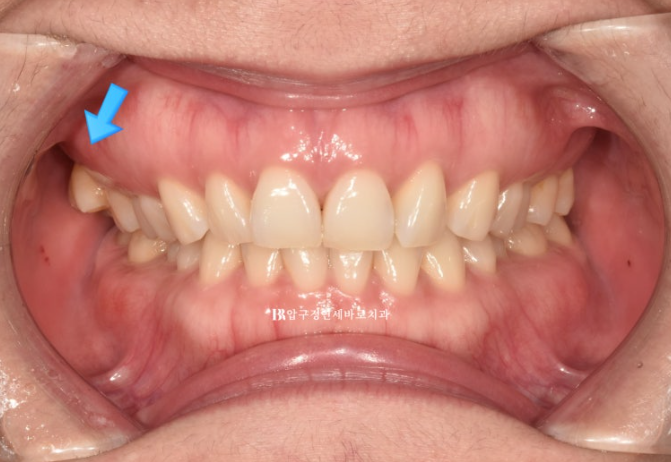

중심선 불일치 그리고 오른쪽의 맨 뒤 큰 어금니가 바깥으로 나가 있는 가위교합이 정면에서도 잘 보입니다.

23.07

오른쪽 맨 뒤 큰 어금니의 가위교합이 보이고 왼쪽은 송곳니와 앞니 사이 벌어진 공간이 보입니다.

인비절라인 라이트로 이 모든 것을 해결하고 치료에 들어갑니다.